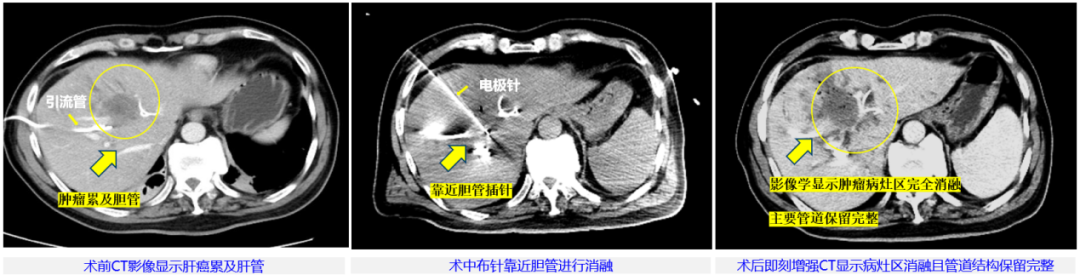

本次治疗病例为57岁男性,临床诊断肝内胆管细胞癌局部转移,侵犯肝门伴梗阻性黄疸,主病灶45mm×36mm,已行双侧PTBD(经皮经肝胆管穿刺引流术)减黄处理。由于病灶位于肝门部,紧邻左侧门静脉及胆囊,这里密布肝动脉、门静脉和胆管等重要脉管结构,无法进行手术切除根治,也不适合各种冷/热消融治疗。董家鸿牵头肝胆胰中心多学科讨论后决定,为患者进行具有脉管保护优势的“微纳刀”消融治疗。

患者影像

整个手术过程中,患者行局部麻醉,在B超联合CT引导下使用“微纳刀”通过单针对病灶区进行消融,消融过程历时15分钟。术中未使用任何肌松剂,也没有采用气管麻醉,患者始终处于清醒状态,可与医生交流。脉冲施加过程中未见肌肉有明显收缩反应,患者也无明显的疼痛感觉,术后即刻增强CT复查发现,肿瘤病灶区在影像学上已显示全部消融,邻近胆管、血管未见损伤。随后患者安全返回病房,术中术后生命体征平稳、未发现不良反应。